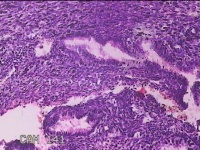

宫颈管内膜组织

性别

女

年龄

39岁

临床诊断

子宫异常出血 子宫内膜不典型增生?子宫内膜占位性病变待查 慢性宫颈炎

一般病史

阴道流血3天,增多1小时。

标本名称

大体所见

灰白暗红色不规则碎组织1.8x1.3x0.3cm一堆。

子宫颈管内膜和子宫内膜组织,没有什么大问题。